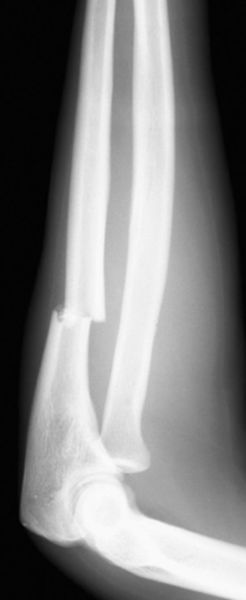

前臂双骨折

疼痛科怎么理疗疼痛科医生、康复理疗科医生、针刀针灸医生应掌握的常见骨科疾病X光片_https://www.jmylbn.com_新闻资讯_第17张